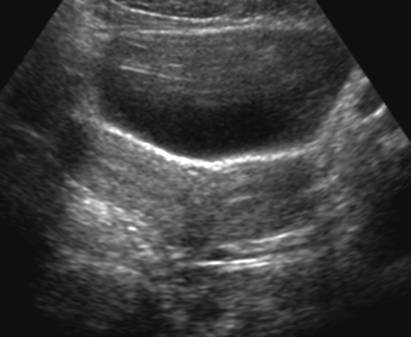

Utérus cloisonné (Cliché : Dr. C. TALMANT)